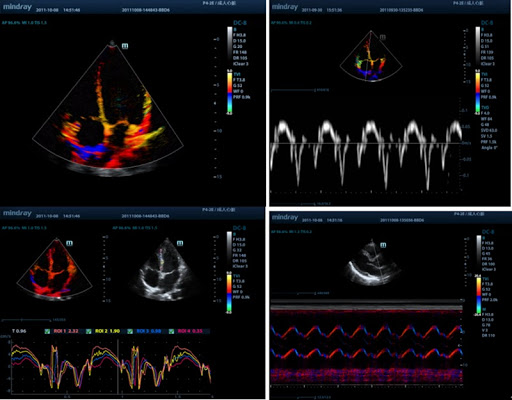

Free Xros CM

Огибающий (нелинейный) анатомический М-режим. Позволяет получать полную информацию о движении сердечной мышцы на различных фазах и одновременно определять степень синхронизации миокарда. Точность результатов обеспечивается высокой частотой кадров.

Тканевая допплеровская визуализация (TDI)

С помощью тканевой допплеровской визуализации можно определять количественные показатели движения и функционирования сердечной мышцы, используя режимы полной визуализации для быстрой и непосредственной диагностики.

AutoEF

Интеллектуальный способ анализа изображений двухмерной эхокардиографии для автоматического распознавания диастолических и систолических кадров и вывода результатов КДО, КСО, реакции выброса и т. д. методом Симпсона